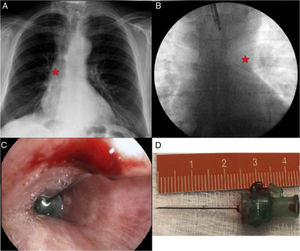

Radiological evidence from the day of the FB showed the presence of a radiopaque structure located in the bronchus intermedius (Fig. 1) not visible on the CT scan conducted 2 weeks previously. FB revealed a sharp metallic foreign body, located at that time within the left main bronchus, visible under fluoroscopy (Fig. 1). We used a 4.2mm Radial Jaw™ clamp (Boston Scientific) for the endoscopic removal of an intramuscular needle 2.5cm in length. The beveled section that was embedded in the anteromedial wall of the left main bronchus had to be removed prior to complete withdrawal (Fig. 1), and a hemostatic surgical clamp was needed for safe extraction of the foreign body via the tracheostomy. The patient was interviewed again. He reported that he had dropped the foreign body after cleaning the tracheostomy with saline solution, and that hemoptysis had been self-limited.